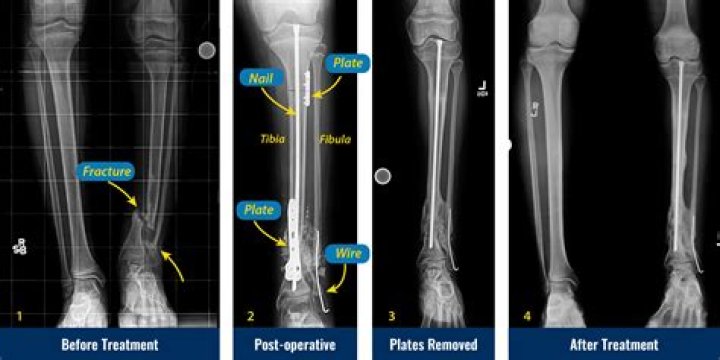

Congenital Pseudoarthrosis Treatment by Paley Cross Union Protocol

Congenital pseudarthrosis of the tibia is a shin bone fracture in children that has not healed. It normally presents before a child turns two years old.

What is tibial pseudarthrosis?

Tibial pseudarthrosis is the name given to a fracture of the tibia (the larger of the two bones in the lower leg) that does not heal correctly.